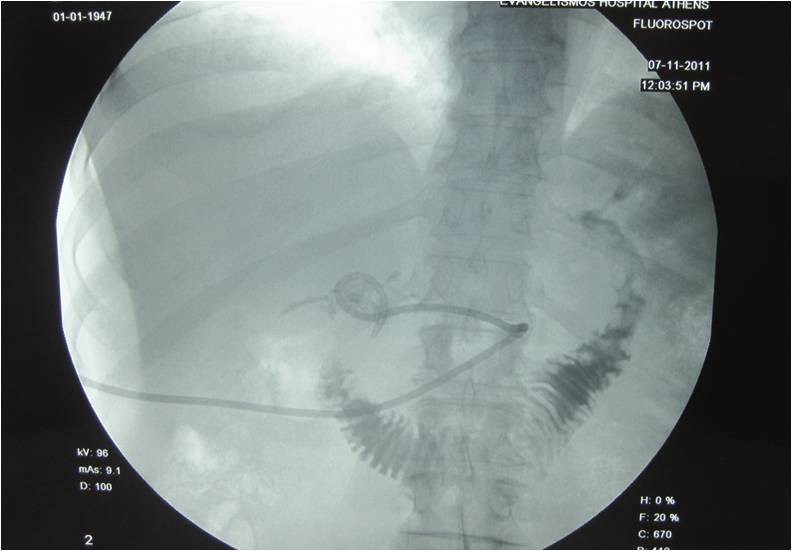

- Roentgenogram depicting the nephrostomy catheter in the duodenum after the infusion of contrast media through the catheter

- Catheter placement next to the duodenum for prevention of fluid collection